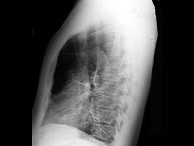

85、单项选择题

女性,46岁。呼吸困难入院。胸部X线平片如下图。右侧肋膈角区垂直于胸壁内侧面的线状影为()

A.KerleyA线

B.KerleyB线

C.KerleyC线

D.盘状肺不张

E.胸腔积液